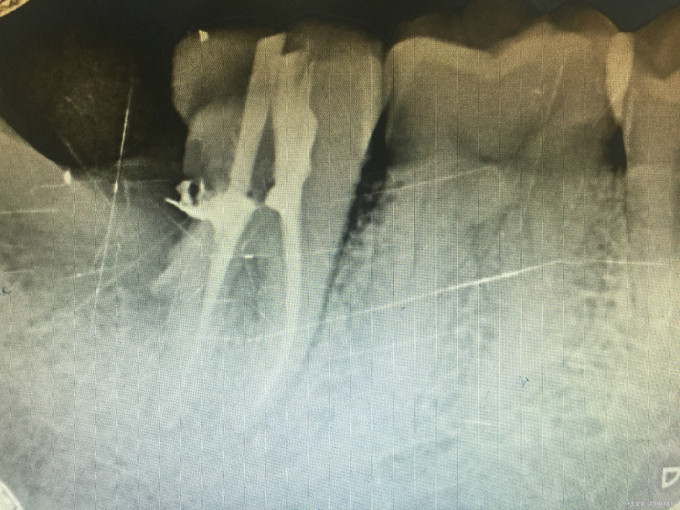

临床检查:47远中龋坏,探疼(+),冷(++),叩(-),松动度(-),牙周正常. 48未完全萌出, 辅助检查:X线示47远中龋坏累积髓腔,48近中水平阻生。

诊断:47牙髓炎,48阻生齿 治疗:经患者知情同意后,48拔除,47局麻去腐降牙合,开髓拔髓寻找根管口,建立直线通路,扩通根管,确定工作长度。S3/EDTA凝胶镍钛器械,低浓度次氯酸钠冲洗根管,预备至35/04,氢氧化钙诊间封药,一周后复诊,试主尖X线示恰充,试干根管,导AH-PLUS糊剂,VDW热压胶垂直加压根充,术后见根管恰充,暂封调合抛光。观察桩冠修复。